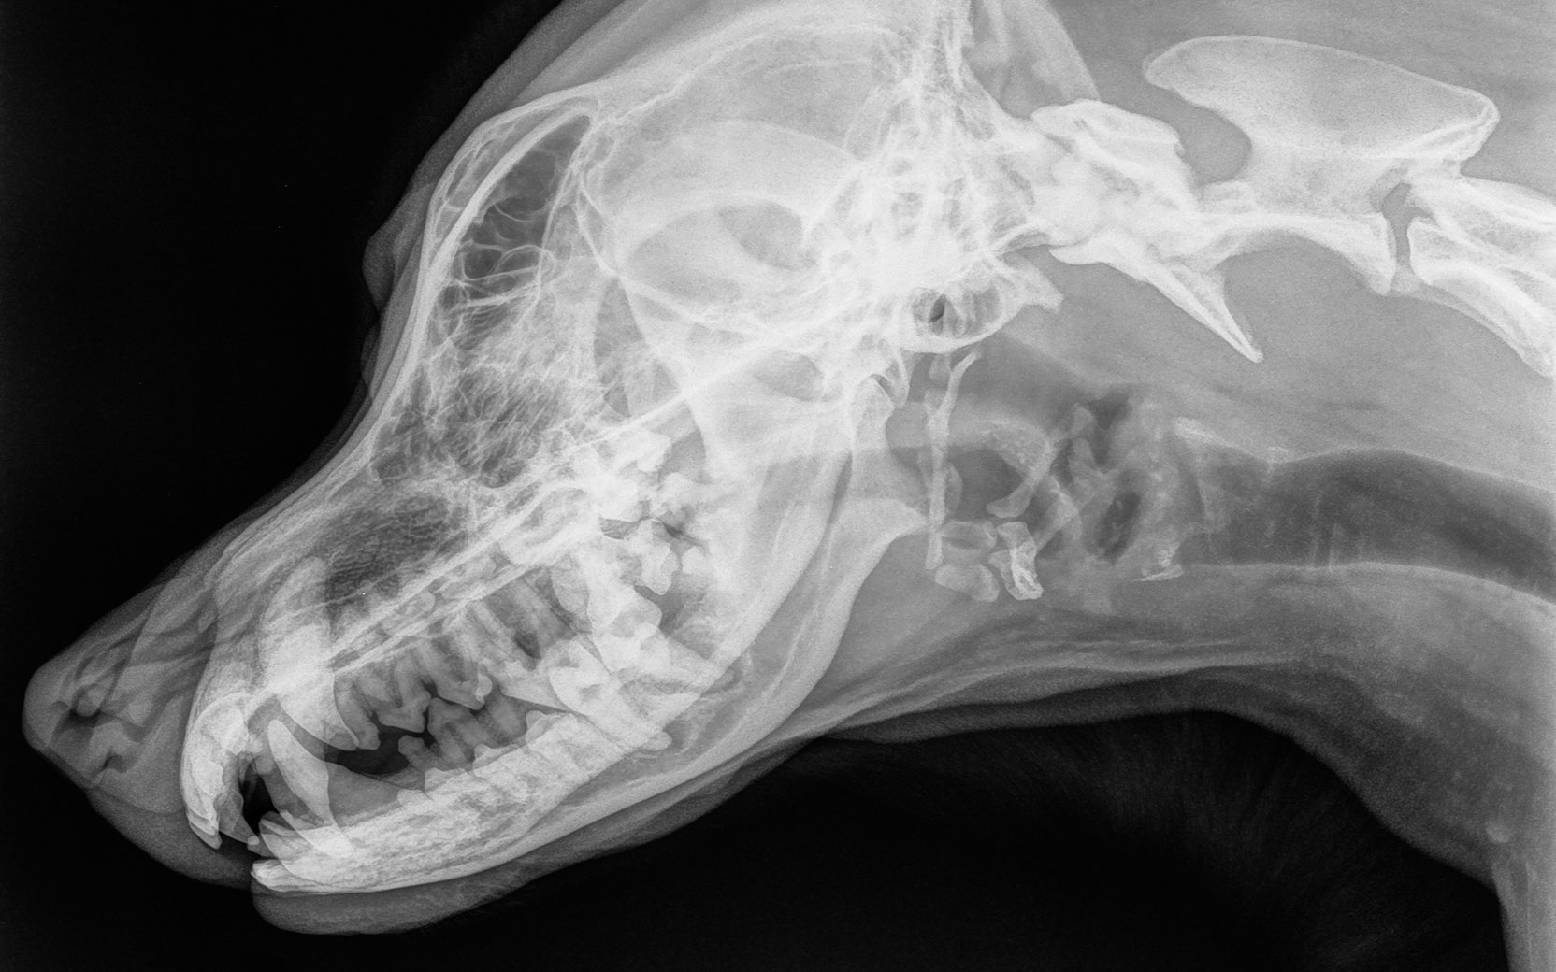

Der Tierarzt wird eine eingehende klinische Untersuchung durchführen und sich dann spezielle der Maulhöhle des Tieres widmen. Dabei ist es wichtig, dass das gesamte Gebiss und das Zahnfleisch genau untersucht wird. Um eine sichere Diagnose stellen zu können, sind einige weiterführende Untersuchungen notwendig. Mit Hilfe spezieller Instrumente wird die Tiefe der Zahnfleischfurche gemessen, die wichtige Informationen über den Grad der Erkrankung liefert. Eine Röntgenuntersuchung ist ebenfalls immer anzuraten, da die genaue Lokalisation und das Ausmaß der Schäden von außen oftmals nicht zu beurteilen ist. Tiefer liegende Schäden an Wurzel und Kieferknochen können röntgenologisch dargestellt werden.